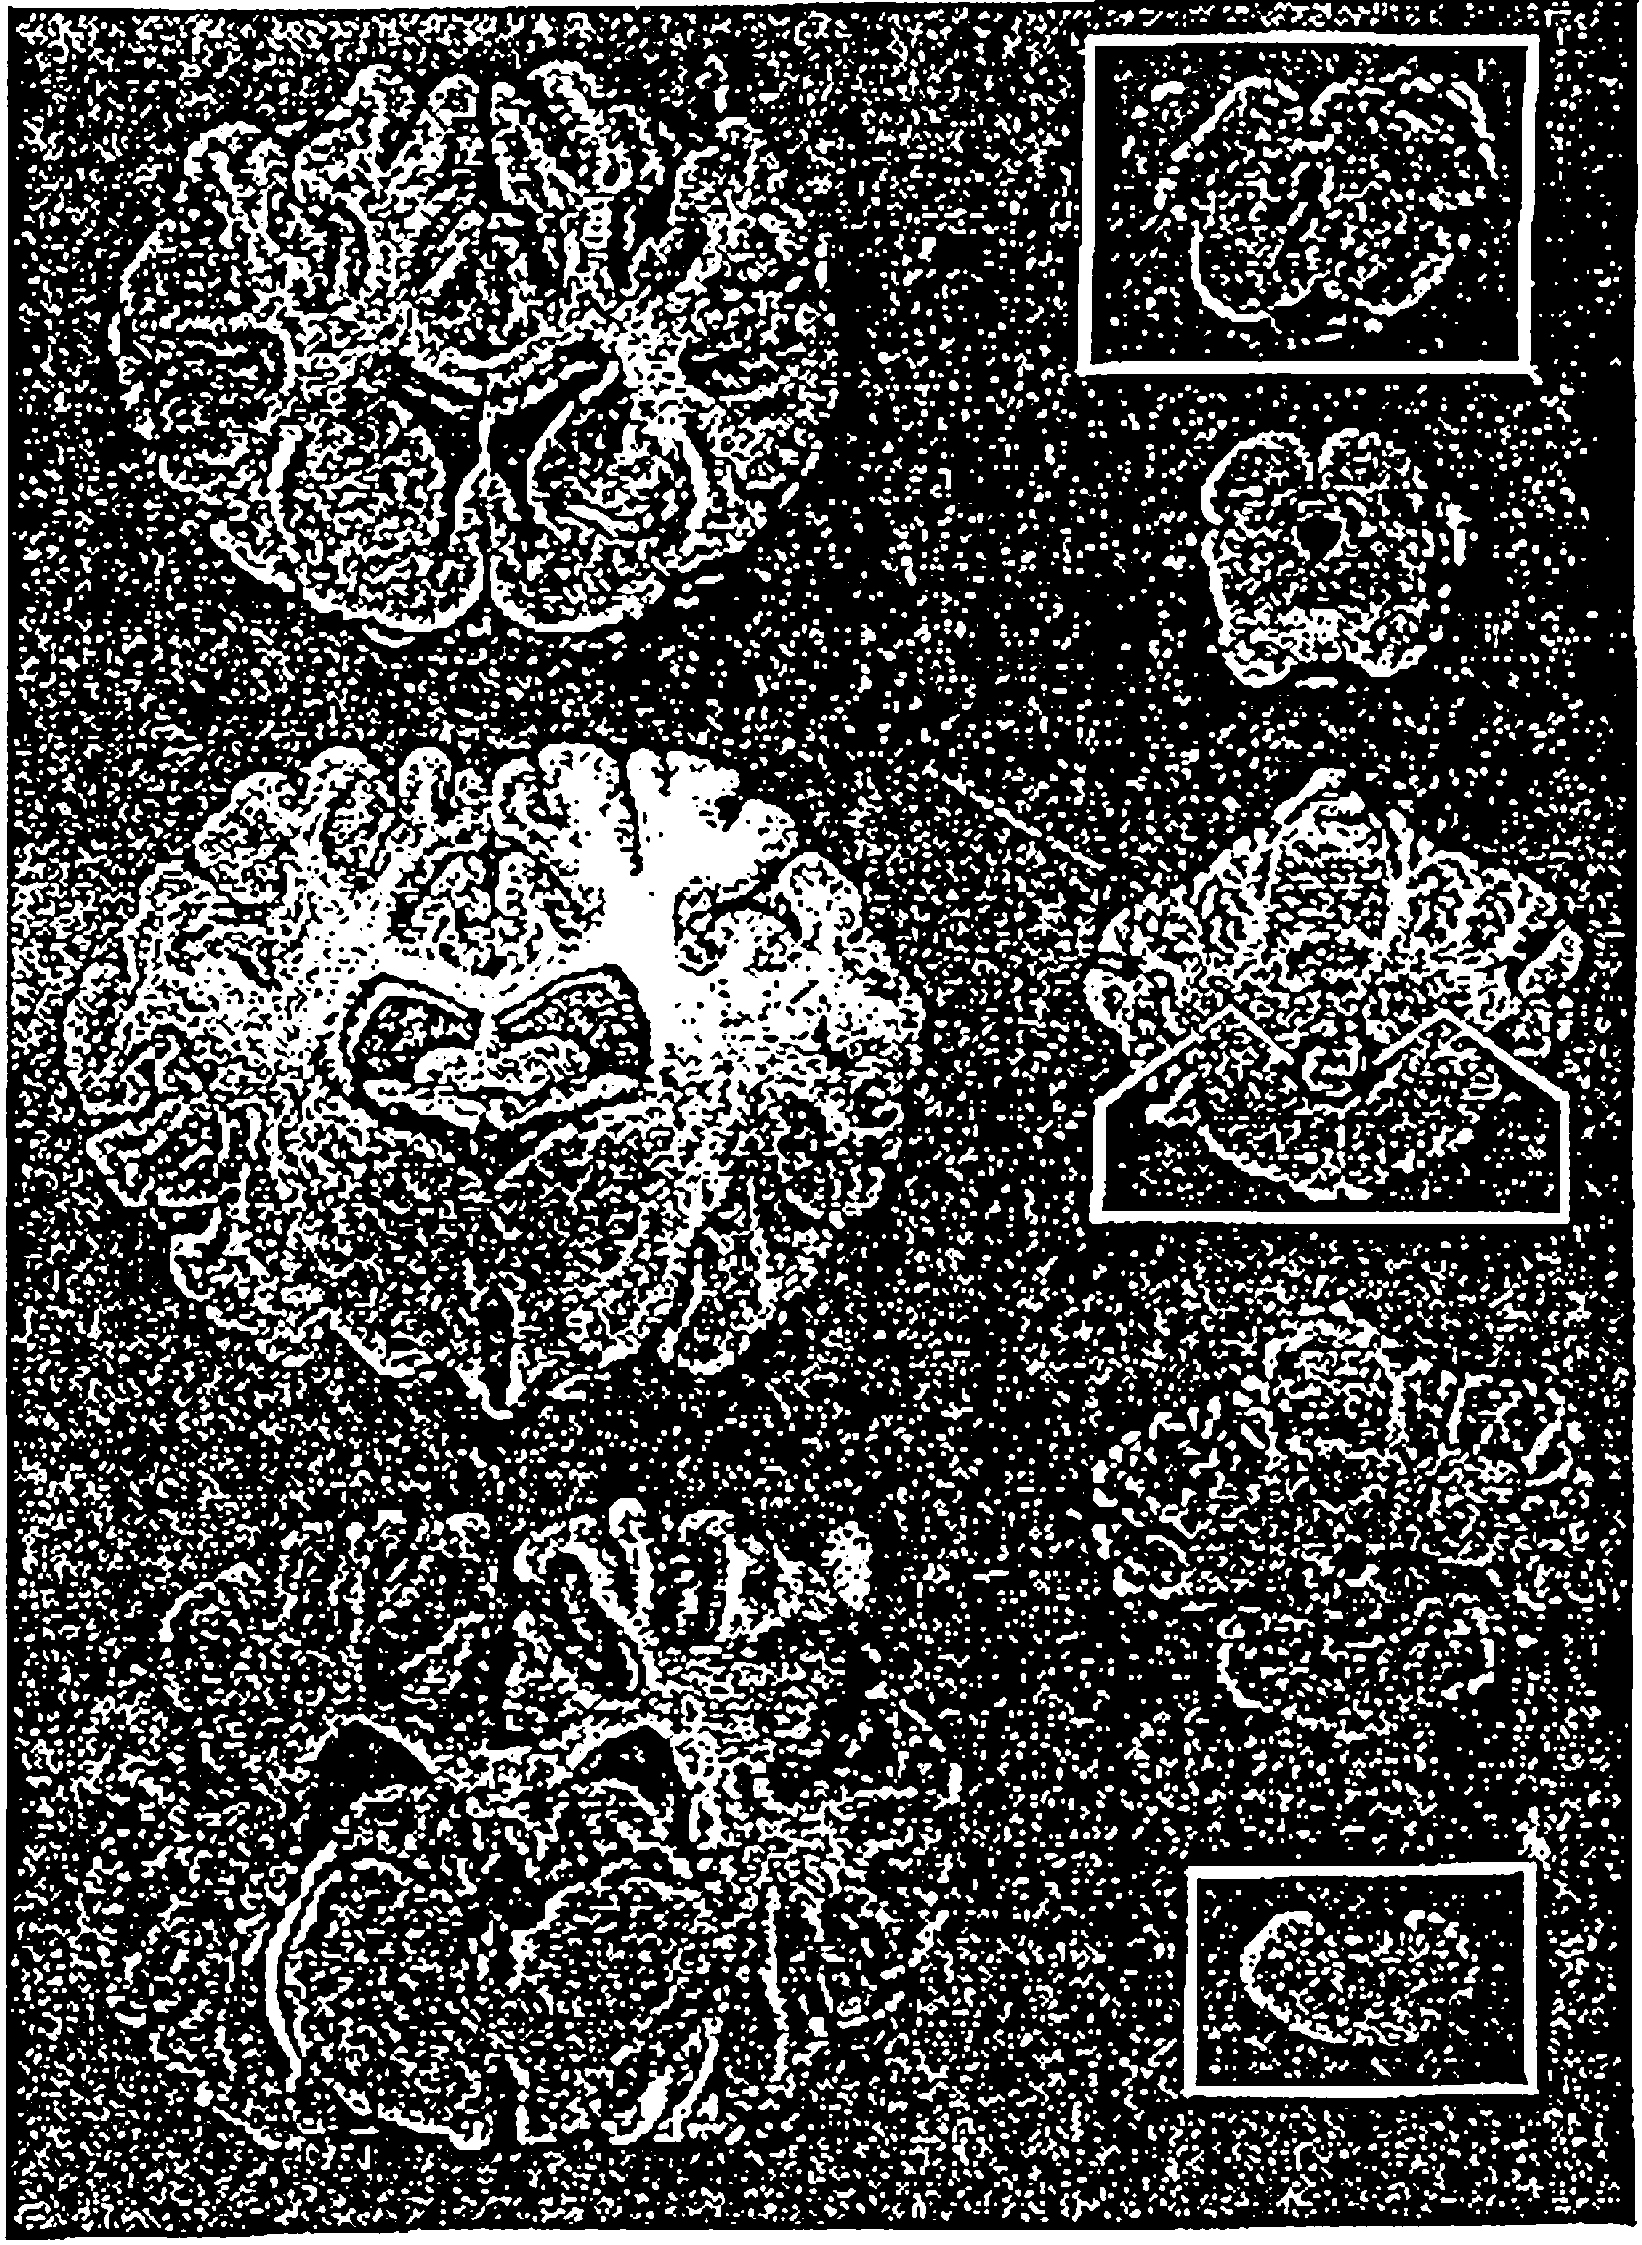

Рис. 3. Поперечные срезы головного мозга крупного рогатого

скота. Кусочки стволовой части, указанные на рис. 2

для вырезки с целью проведения гистологической диагностики

губкообразной энцефалопатии, обведены.

- на губкообразную энцефалопатию крупного рогатого скота - из продолговатого мозга (области задвижки и задних ножек мозжечка), среднего мозга (область ростральных холмов) - рис. 2 и 3;